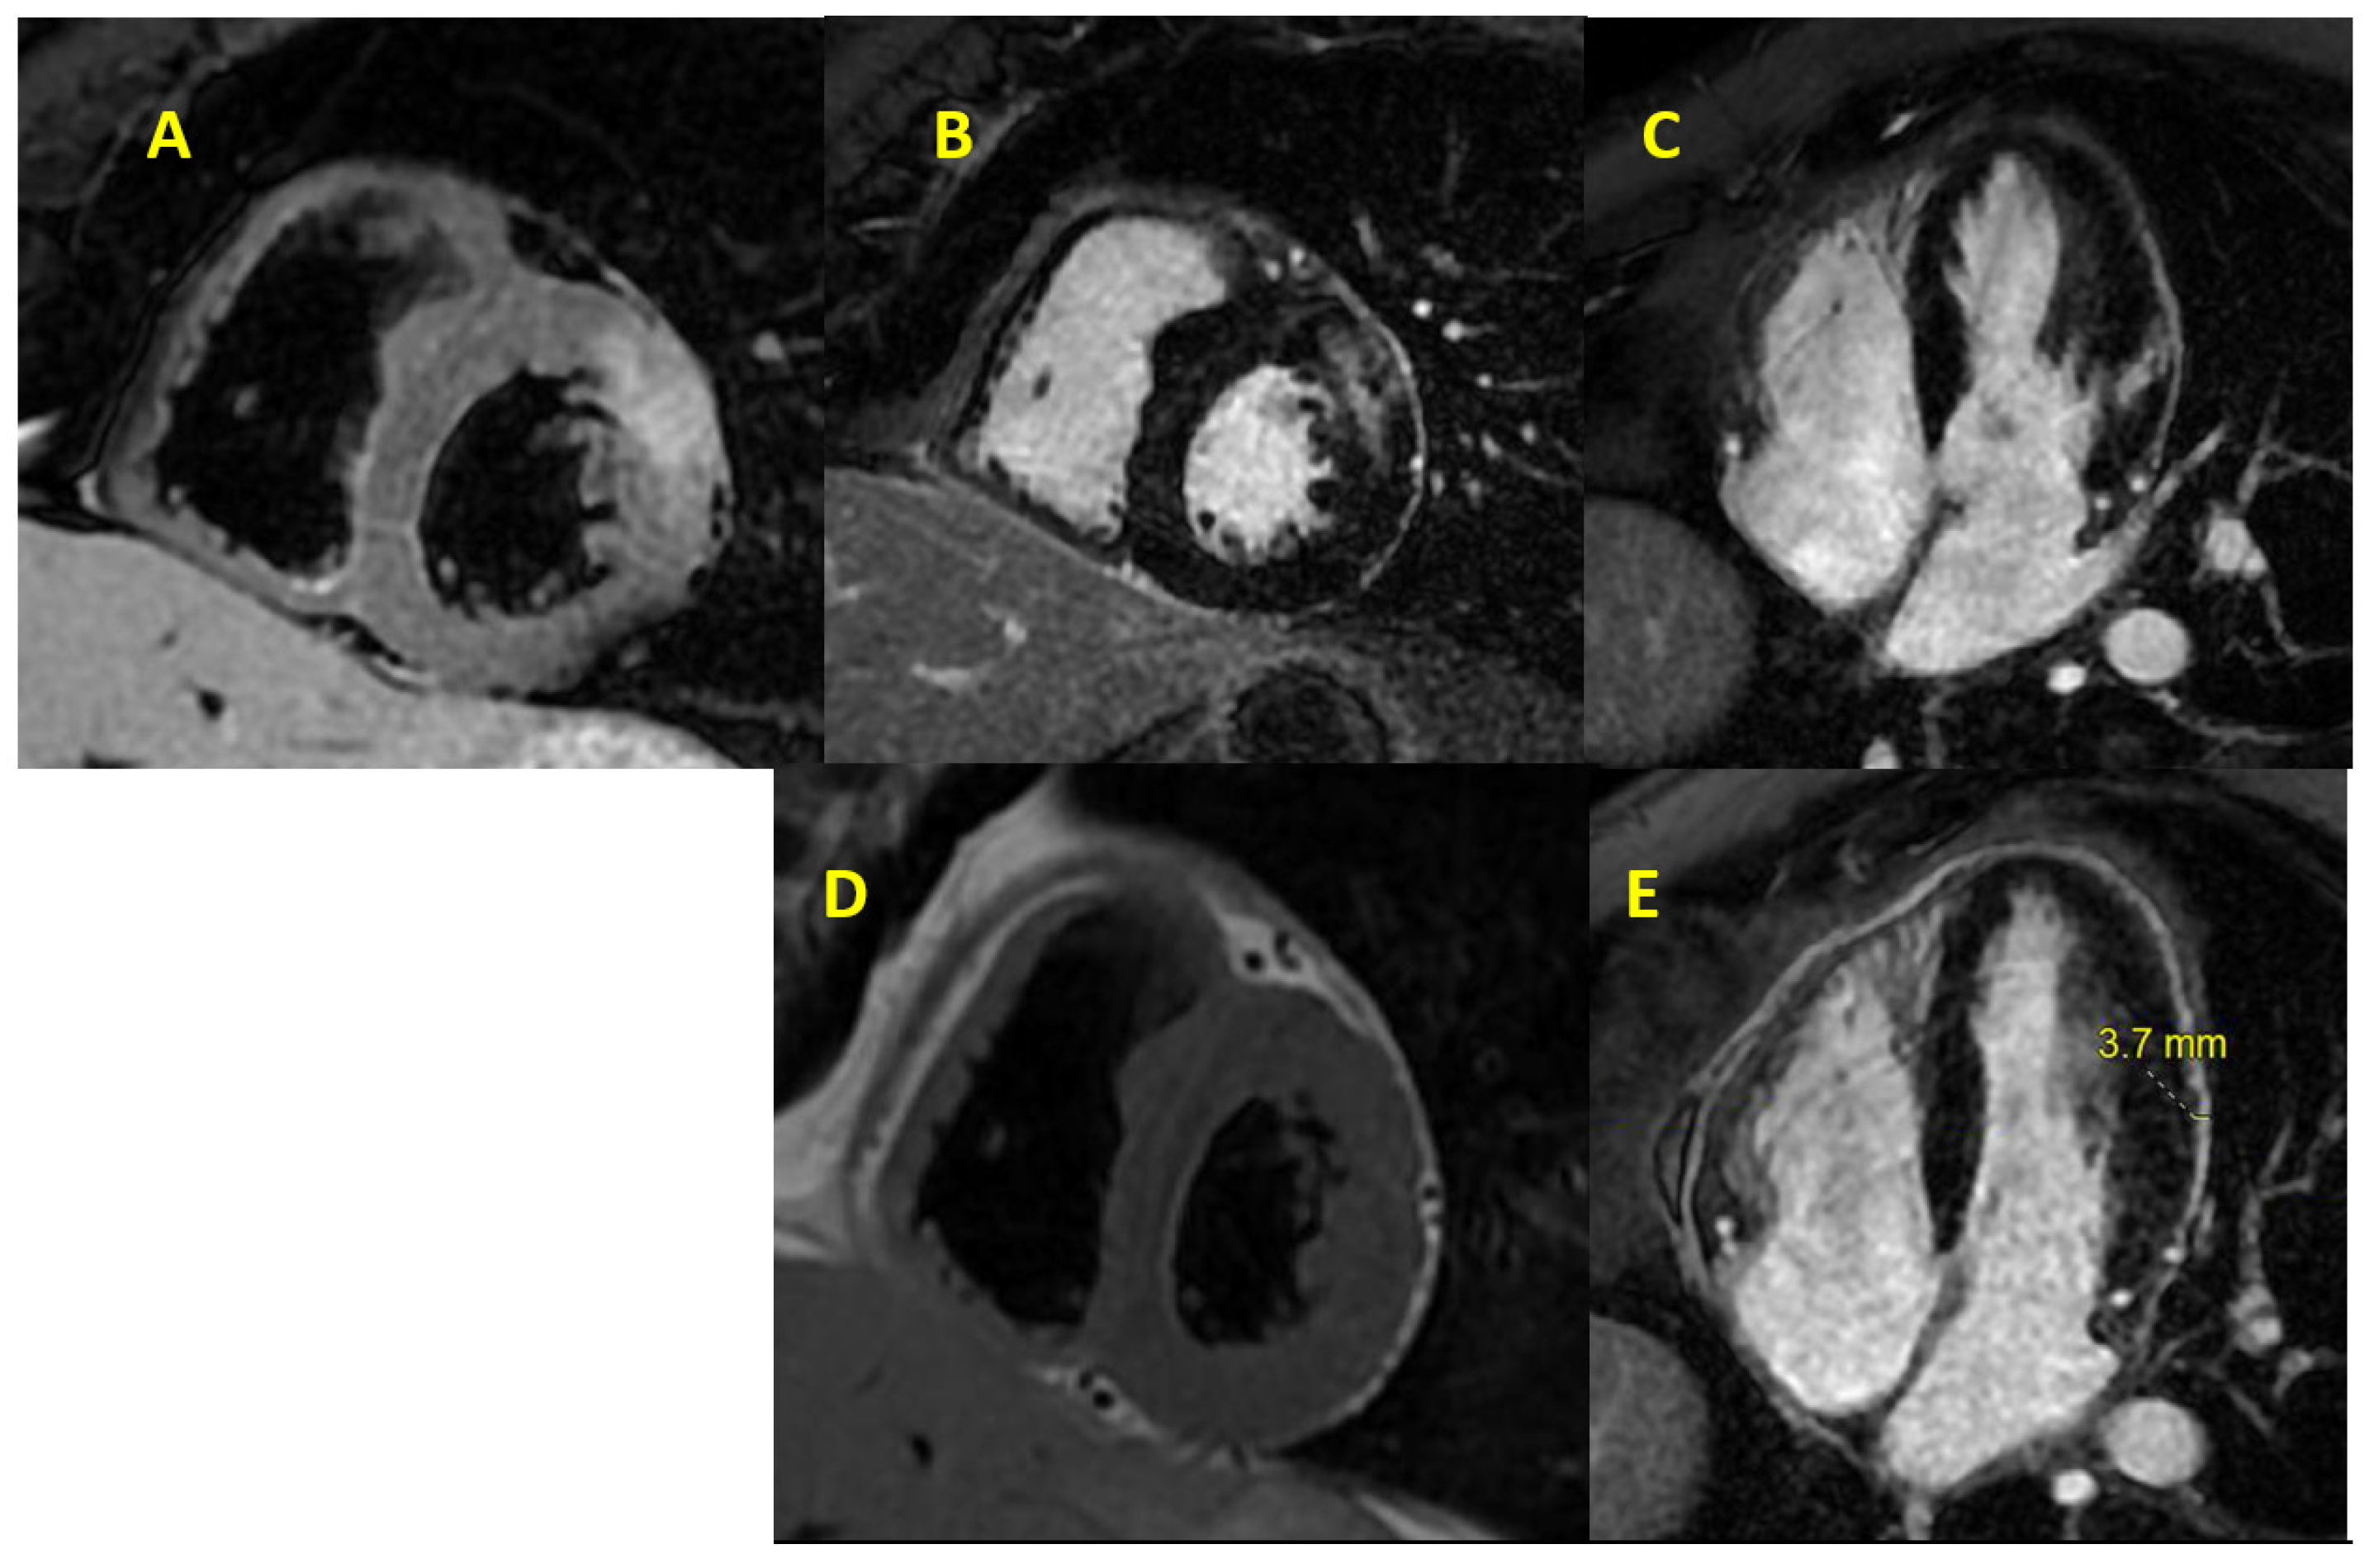

- Esposito, A.; Palmisano, A.; Barbera, M.; Vignale, D.; Benedetti, G.; Spoladore, R.; Ancona, M.B.; Giannini, F.; Oppizzi, M.; Del Maschio, A.; et al. Cardiac Computed Tomography in Troponin-Positive Chest Pain: Sometimes the Answer Lies in the Late Iodine Enhancement or Extracellular Volume Fraction Map. JACC Cardiovasc. Imaging 2019, 12, 745–748. [Google Scholar] [CrossRef]